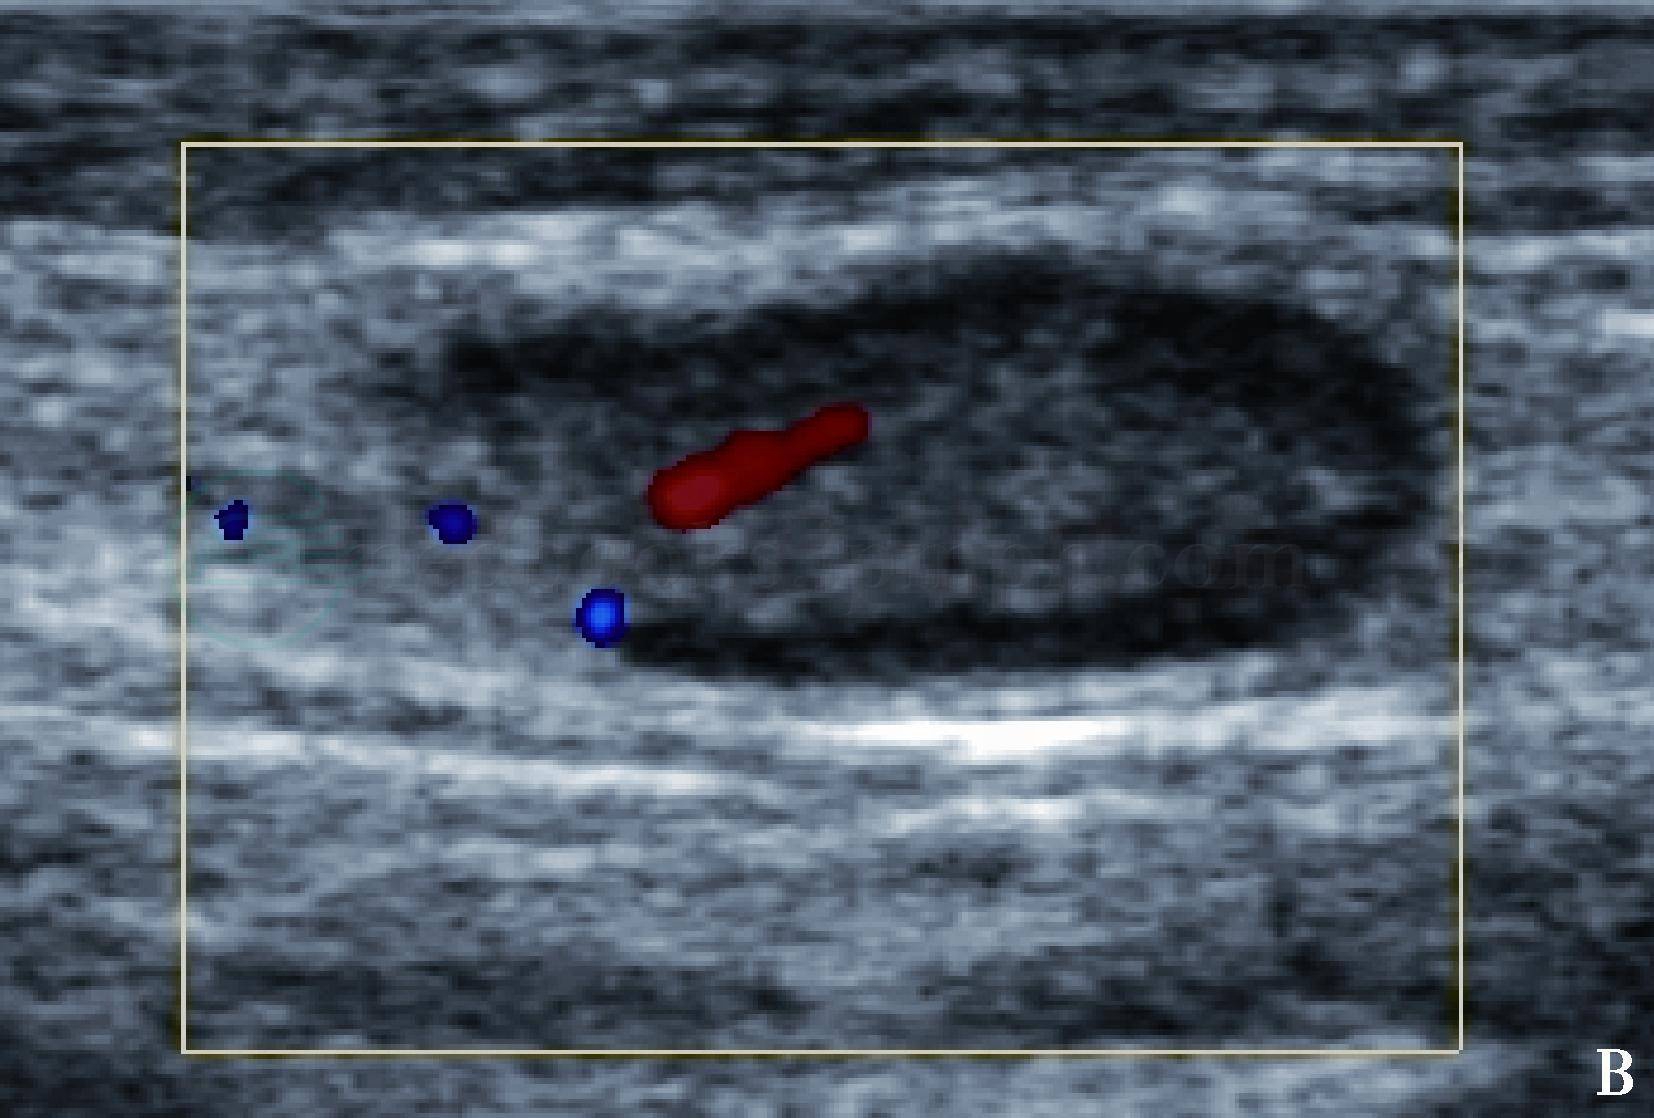

图1 正常颈部淋巴结声像图

彩色多普勒超声显示淋巴结髓质内点状血流